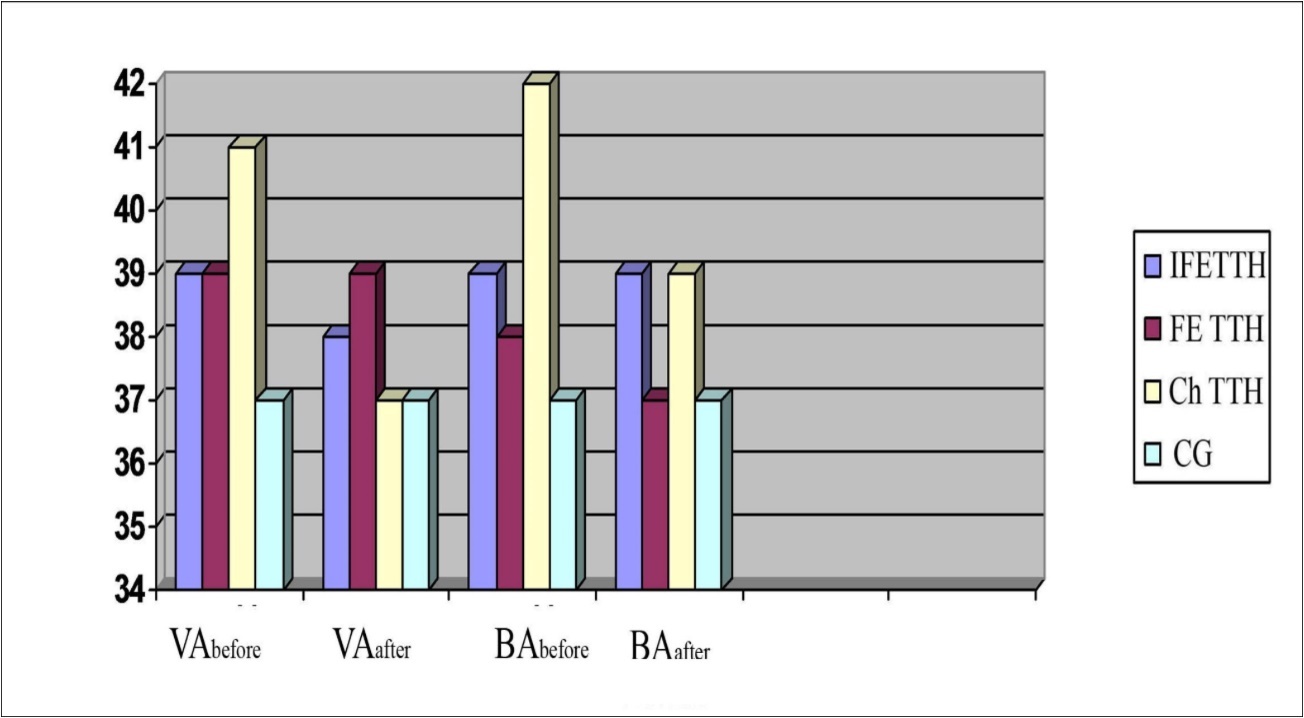

The asymmetry of the maximum systolic blood flow velocity (Vs) in the paired arteries within 20-30% was considered a violation of cerebral hemodynamics, which was detected in 38.7% of patients. An increase in Vs was noted in MCA in patients with Ch TTH and FE TTH compared with the control group (Figure 1, Figure 2A and B).

Figure 1.Parameters of Vs (cm/c) in the main cerebral arteries in a patients with TTH.

The pharmacotherapeutic effect of drug on the dynamics of blood flow indices in the vertebral and basal arteries before and after treatment is shown in Figure 9. The minimal statistical significance (P<0,05) was observed only in the VA (from 41.4±1.3 cm/s to 37.2±1.4 cm/s).

Figure 9.Dynamics of Vs in VA and BA in a patients with TTH during treatment with Noofen